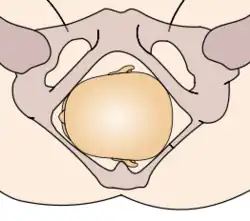

Durante la mecánica del parto, los diámetros menores del feto pasan por los diámetros mayores de la pelvis materna. Con el fin de no quedar encajado en algún punto durante su trayectoria fuera del útero, el neonato pasa por una serie de movimientos naturales que constituyen el mecanismo del parto.

- Encajamiento: el diámetro de la cabeza del feto que va desde un hueso parietal al opuesto, llamado diámetro biparietal, alcanza el estrecho superior de la pelvis a nivel de las espinas isquiáticas. Por lo general ocurre en la fase tardía del embarazo, justo al iniciarse el trabajo de parto.

La relación de la fontanela posterior con la pelvis materna determina el diagnóstico de posición. Se distinguen ocho posiciones en la presentación de vértice: I. Occípito ilíaca izquierda anterior (OIIA) en que la fontanela posterior se ubica hacia delante en relación con la pelvis materna y además a la izquierda de la madre. La sutura sagital está orientada oblicuamente. II. Sucesivamente dependiendo de la ubicación de la fontanela posterior (porque la pelvis es siempre la misma) las posiciones serán:

- Occípito púbica OP

- Occípito sacra OS[17]